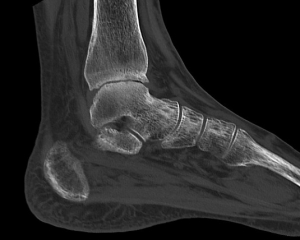

整形領域CT

細かくデータを収集することにより、いろいろな断面で再構成することができます。レントゲン撮影では見えにくい、細かな骨折の診断に有用です。

足関節(矢状断)MPR表示